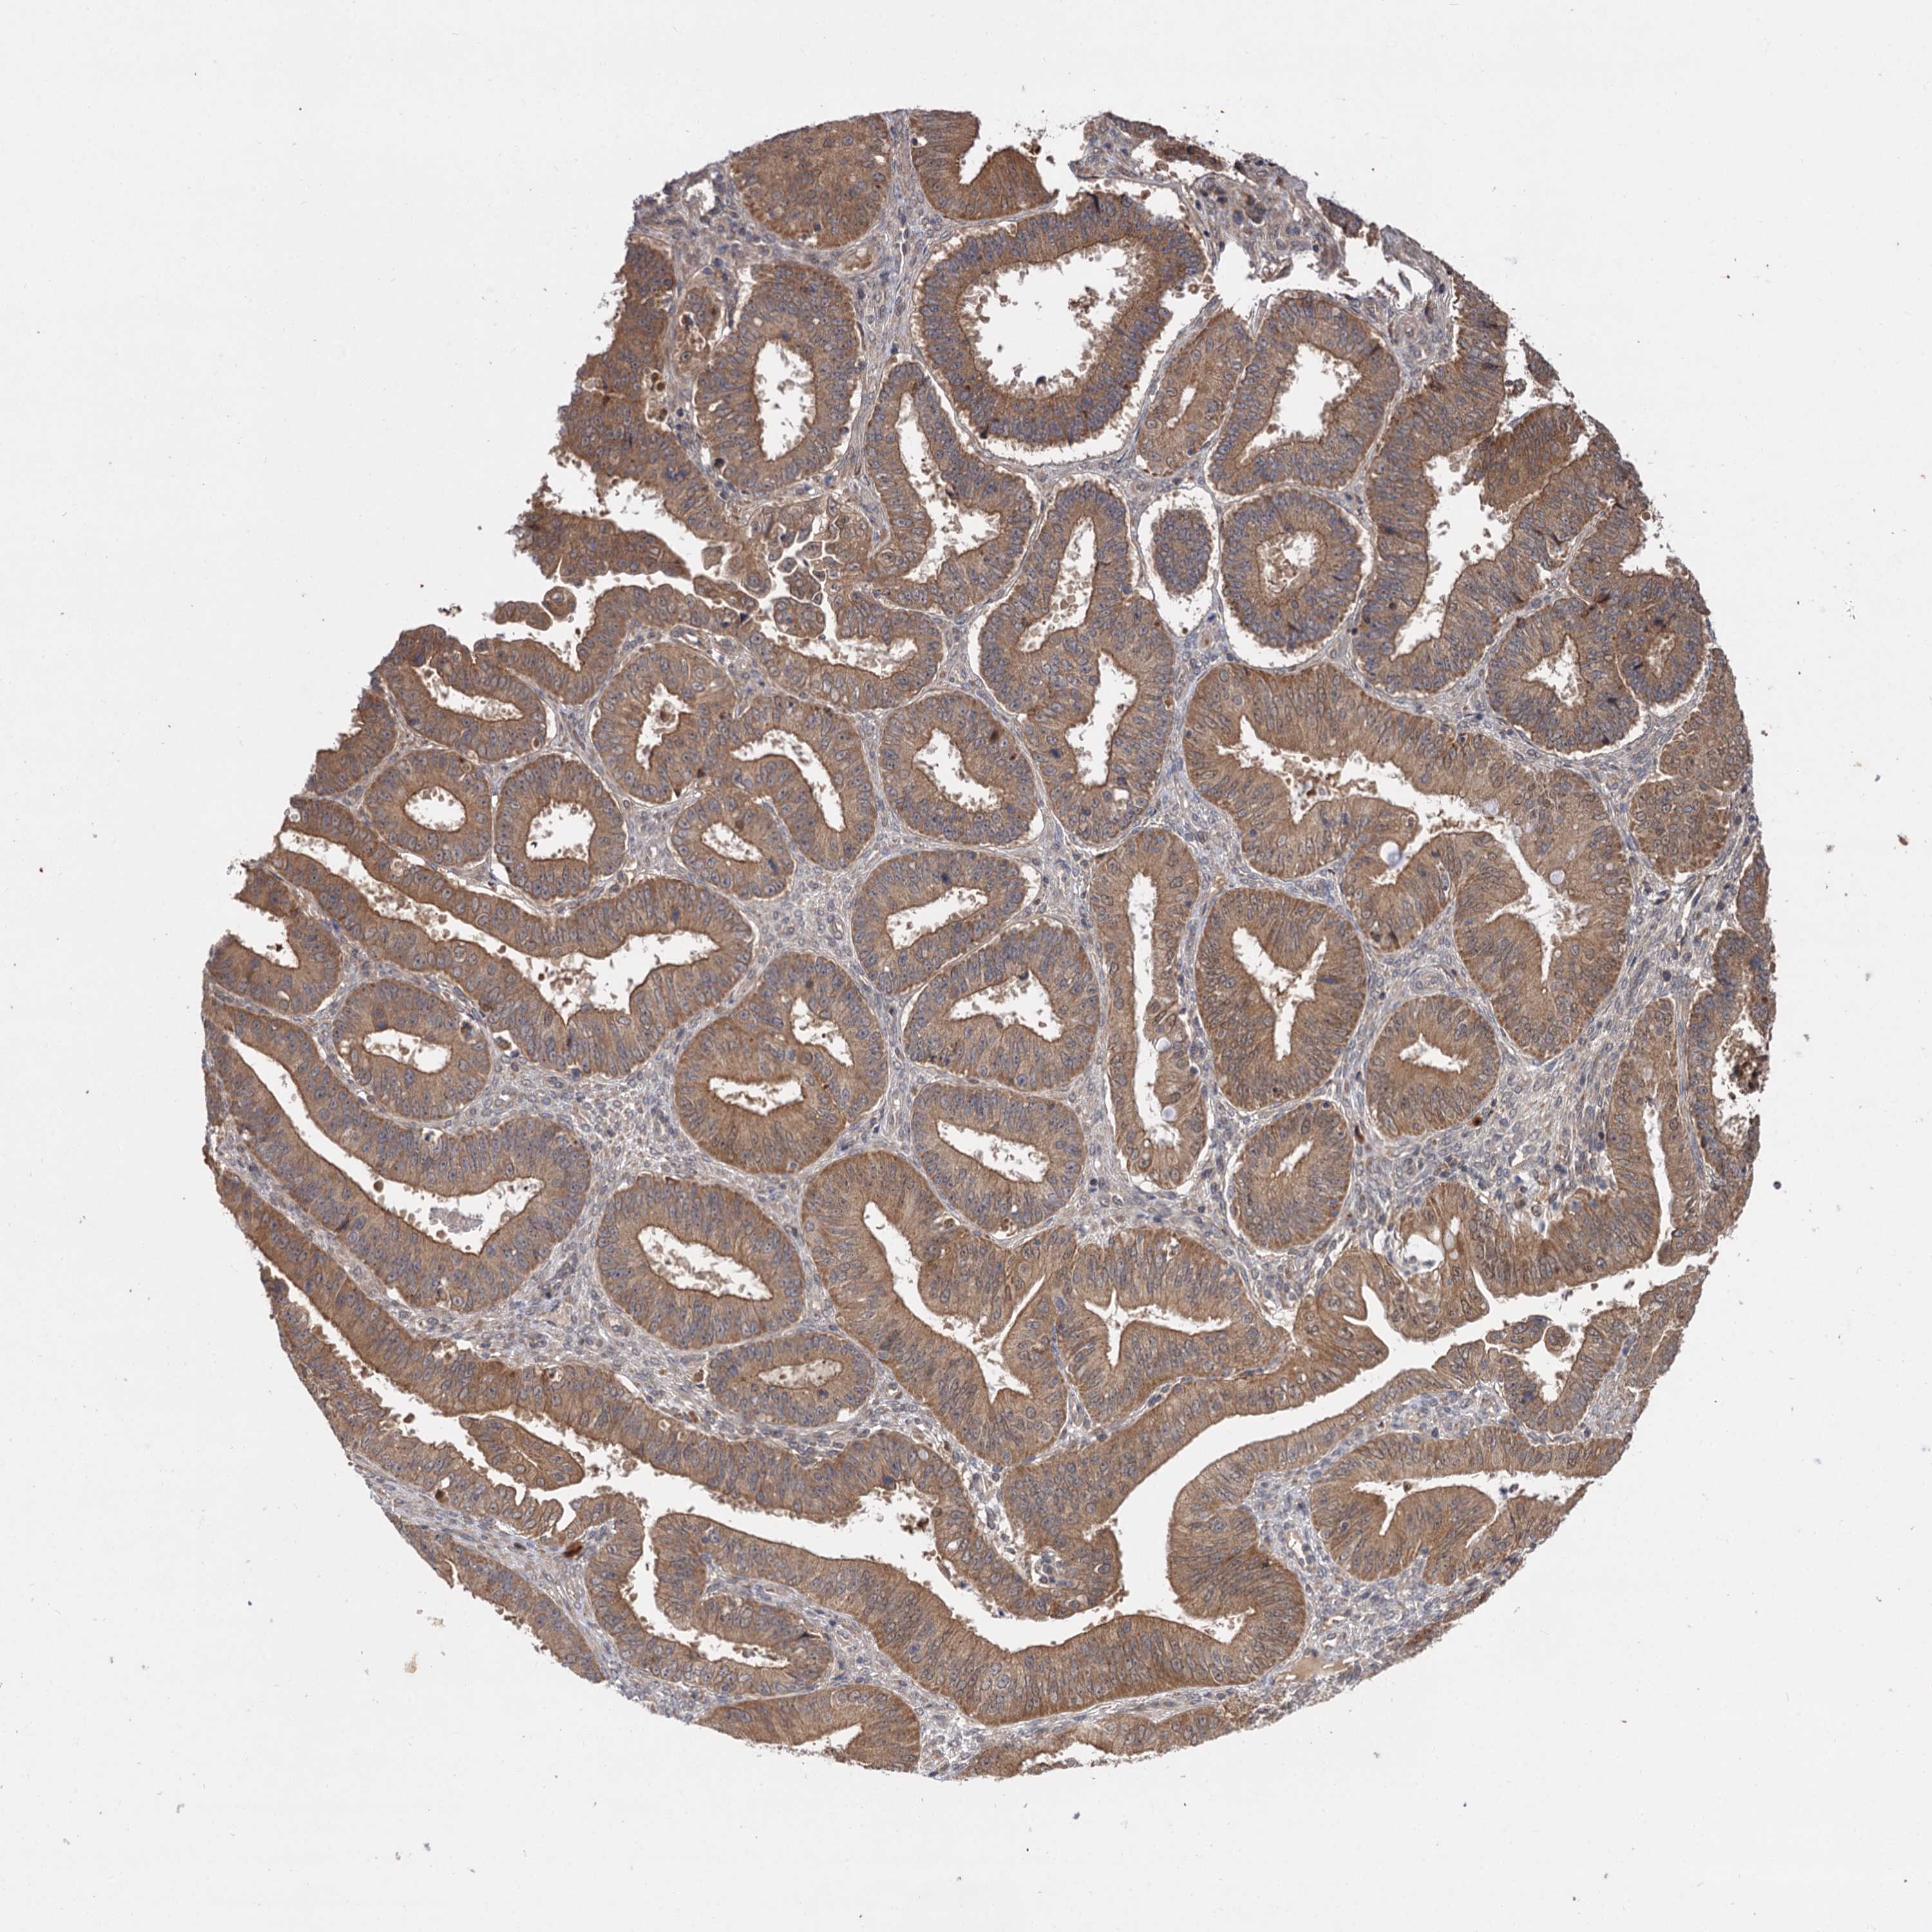

OVARIAN CANCER - Protein expressioni

A mouse-over function shows sample information and annotation data. Click on an image to view it in a full screen mode. Samples can be filtered based on level of antibody staining by selecting one or several of the following categories: high, medium, low and not detected. The assay and annotation is described here.

Note that samples used for immunohistochemistry by the Human Protein Atlas do not correspond to samples in the TCGA dataset.

Antibody stainingi

Antibody staining in the annotated cell types in the current human tissue is reported as not detected, low, medium, or high, based on conventional immunohistochemistry profiling in selected tissues. This score is based on the combination of the staining intensity and fraction of stained cells.

Each image is clickable and will lead to virtual microscopy that enables deeper exploration of all samples and also displays staining intensity scores, fraction scores and subcellular localization as well as patient and tissue information for each sample.

Antibody HPA038850

Antibody HPA038851

Cystadenocarcinoma, serous, NOS